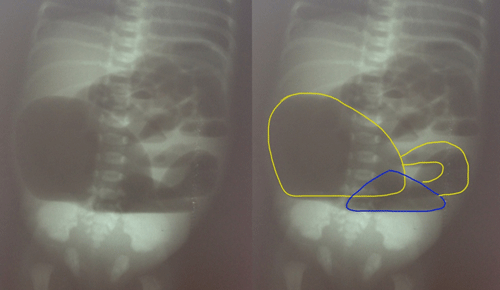

A 3-day-old term male child weighing 2.1 Kg, born by spontaneous vaginal delivery, was admitted with complaints of abdominal distention, meconuria and absent anal opening. This was the first child of the couple who had a non-consanguineous marriage. On examination, there was abdominal distention, poorly developed gluteal folds and an absent anal opening. Plain X-ray abdomen showed two large air fluid levels (Fig. 1). At exploratory laparotomy, Saxena-Mathur classification type 5 congenital pouch colon (CPC) was found. Ileum was opening directly into a hugely distended pouch; there was no appendix. The pouch was dumbbell shaped with normal looking intervening colon of about 5 centimeters. The dumbbell shaped pouch (proximal and distal components) was opening into the bladder through a wide fistula. The proximal part of intervening colon was not communicating with the proximal pouch but was intimately adherent to it. However, the distal part of the intervening colon was communicating with the distal pouch. Both the dumbbell shaped pouch and the terminal colon were receiving blood supply from a prominent marginal vascular pattern (Fig. 2). The distal pouch and intervening normal-looking colon appeared dusky with doubtful viability, so it was excised. Tubularized proximal pouch was brought out as end colostomy. The histopathological examination revealed the disorganized muscles in the muscularis layer of pouch colon; the intervening colon had normal colonic histology though there was evidence of congestion. The child is awaiting definitive repair.

Figure 2: Operative photograph shows proximal and distal colonic pouches with intervening colon.(Left- unedited; right- edited with markings). |